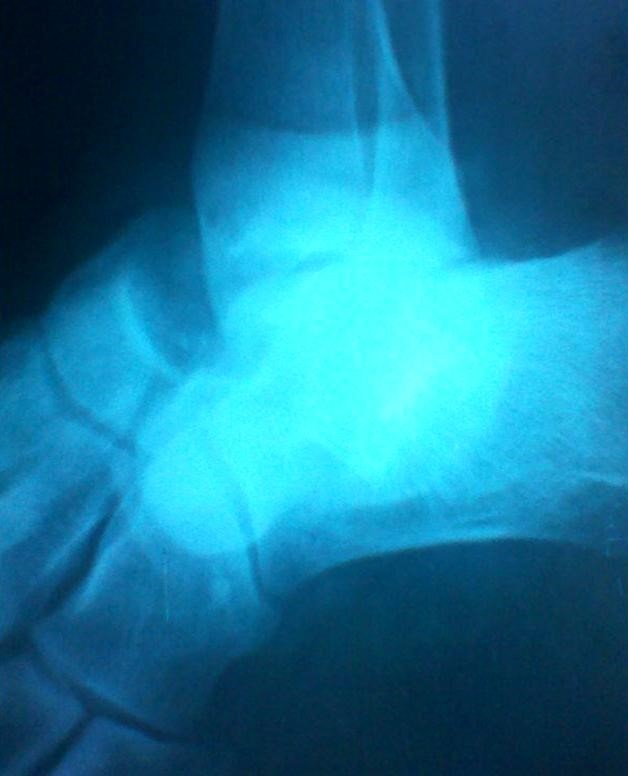

Volver a los detalles del artículo Luxación subastragalina medial